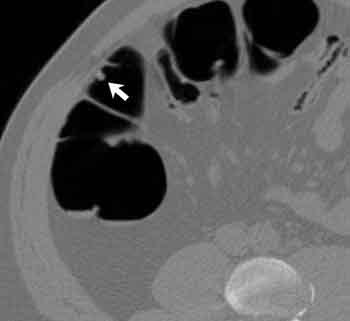

| Eight-millimeter adenomatous polyp in ascending colon seen in 3D endoluminal view (above); in translucent view used to distinguish polyp from stool (below); and in corresponding 2D axial view (bottom). This lesion was missed at prospective conventional colonoscopy, but found after unblinding of VC results. Images courtesy of Dr. Perry Pickhardt. |

Using a threshold-based analysis, VC's sensitivity was 88.7% for polyps 6 mm and larger, 93.9% for polyps 8 mm and larger, and 93.8% for lesions 10 mm and larger. Conventional colonoscopy's sensitivity trended slightly lower: 92.3%, 91.5% and 87.5%, respectively.

VC's accuracy kept improving as the polyp threshold size rose: 80.9% for polyps 6 mm and larger, 92.3% for polyps 8 mm and larger, and 95.9% for polyps 10 mm and larger. As for specificity, virtual colonoscopy was 79.6% specific for polyps 6 mm and larger, 92.2% specific for polyps 8 mm and larger, and 96% specific for polyps 10 mm and larger, Pickhardt said.

When the colonoscope was being withdrawn in conventional colonoscopy, it had a tendency to slip past a few polyps, especially those located on or near haustral folds, he said later. But these polyps tended not to be missed in virtual colonoscopy, and thanks to segmental unblinding of VC results, could be picked up retrospectively with the colonoscope. The use of multidetector-row scanners with thinner collimation also improved VC's performance, he said.